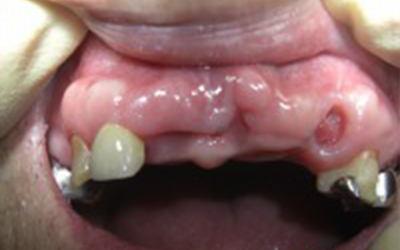

Aさん(70代・男性) インプラント

BEFORE

AFTER

Kさん(60代・女性) インプラント

治療内容

「入れ歯との組み合わせ」

現在入れ歯の人も、少ない本数のインプラントで対応が可能。

通常は全部インプラントがベストですが、入れ歯との組み合わせも可能です。

「入れ歯が安定する」「ガタガタしない」というメリットがあります。